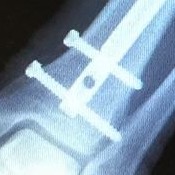

I’m grateful also to the family, friends and professionals who have helped my recovery from the leg-shattering head-on collision between me (dutifully stopped on my bicycle at a Brooklyn traffic light) and a criminally negligent driver (driving on the wrong side of the street and not watching where she was going) in October 2014. On this Ride, I had more power than on the 2015 Ride to New England. But the story isn’t over. Next week, the surgeon will remove these screws

and two more like them, in the hope that this will reduce the pain when I walk. (Cycling is less uncomfortable.) Surgery scares me. But I am determined to restore my former strength. It’s hard to get stronger when something hurts.